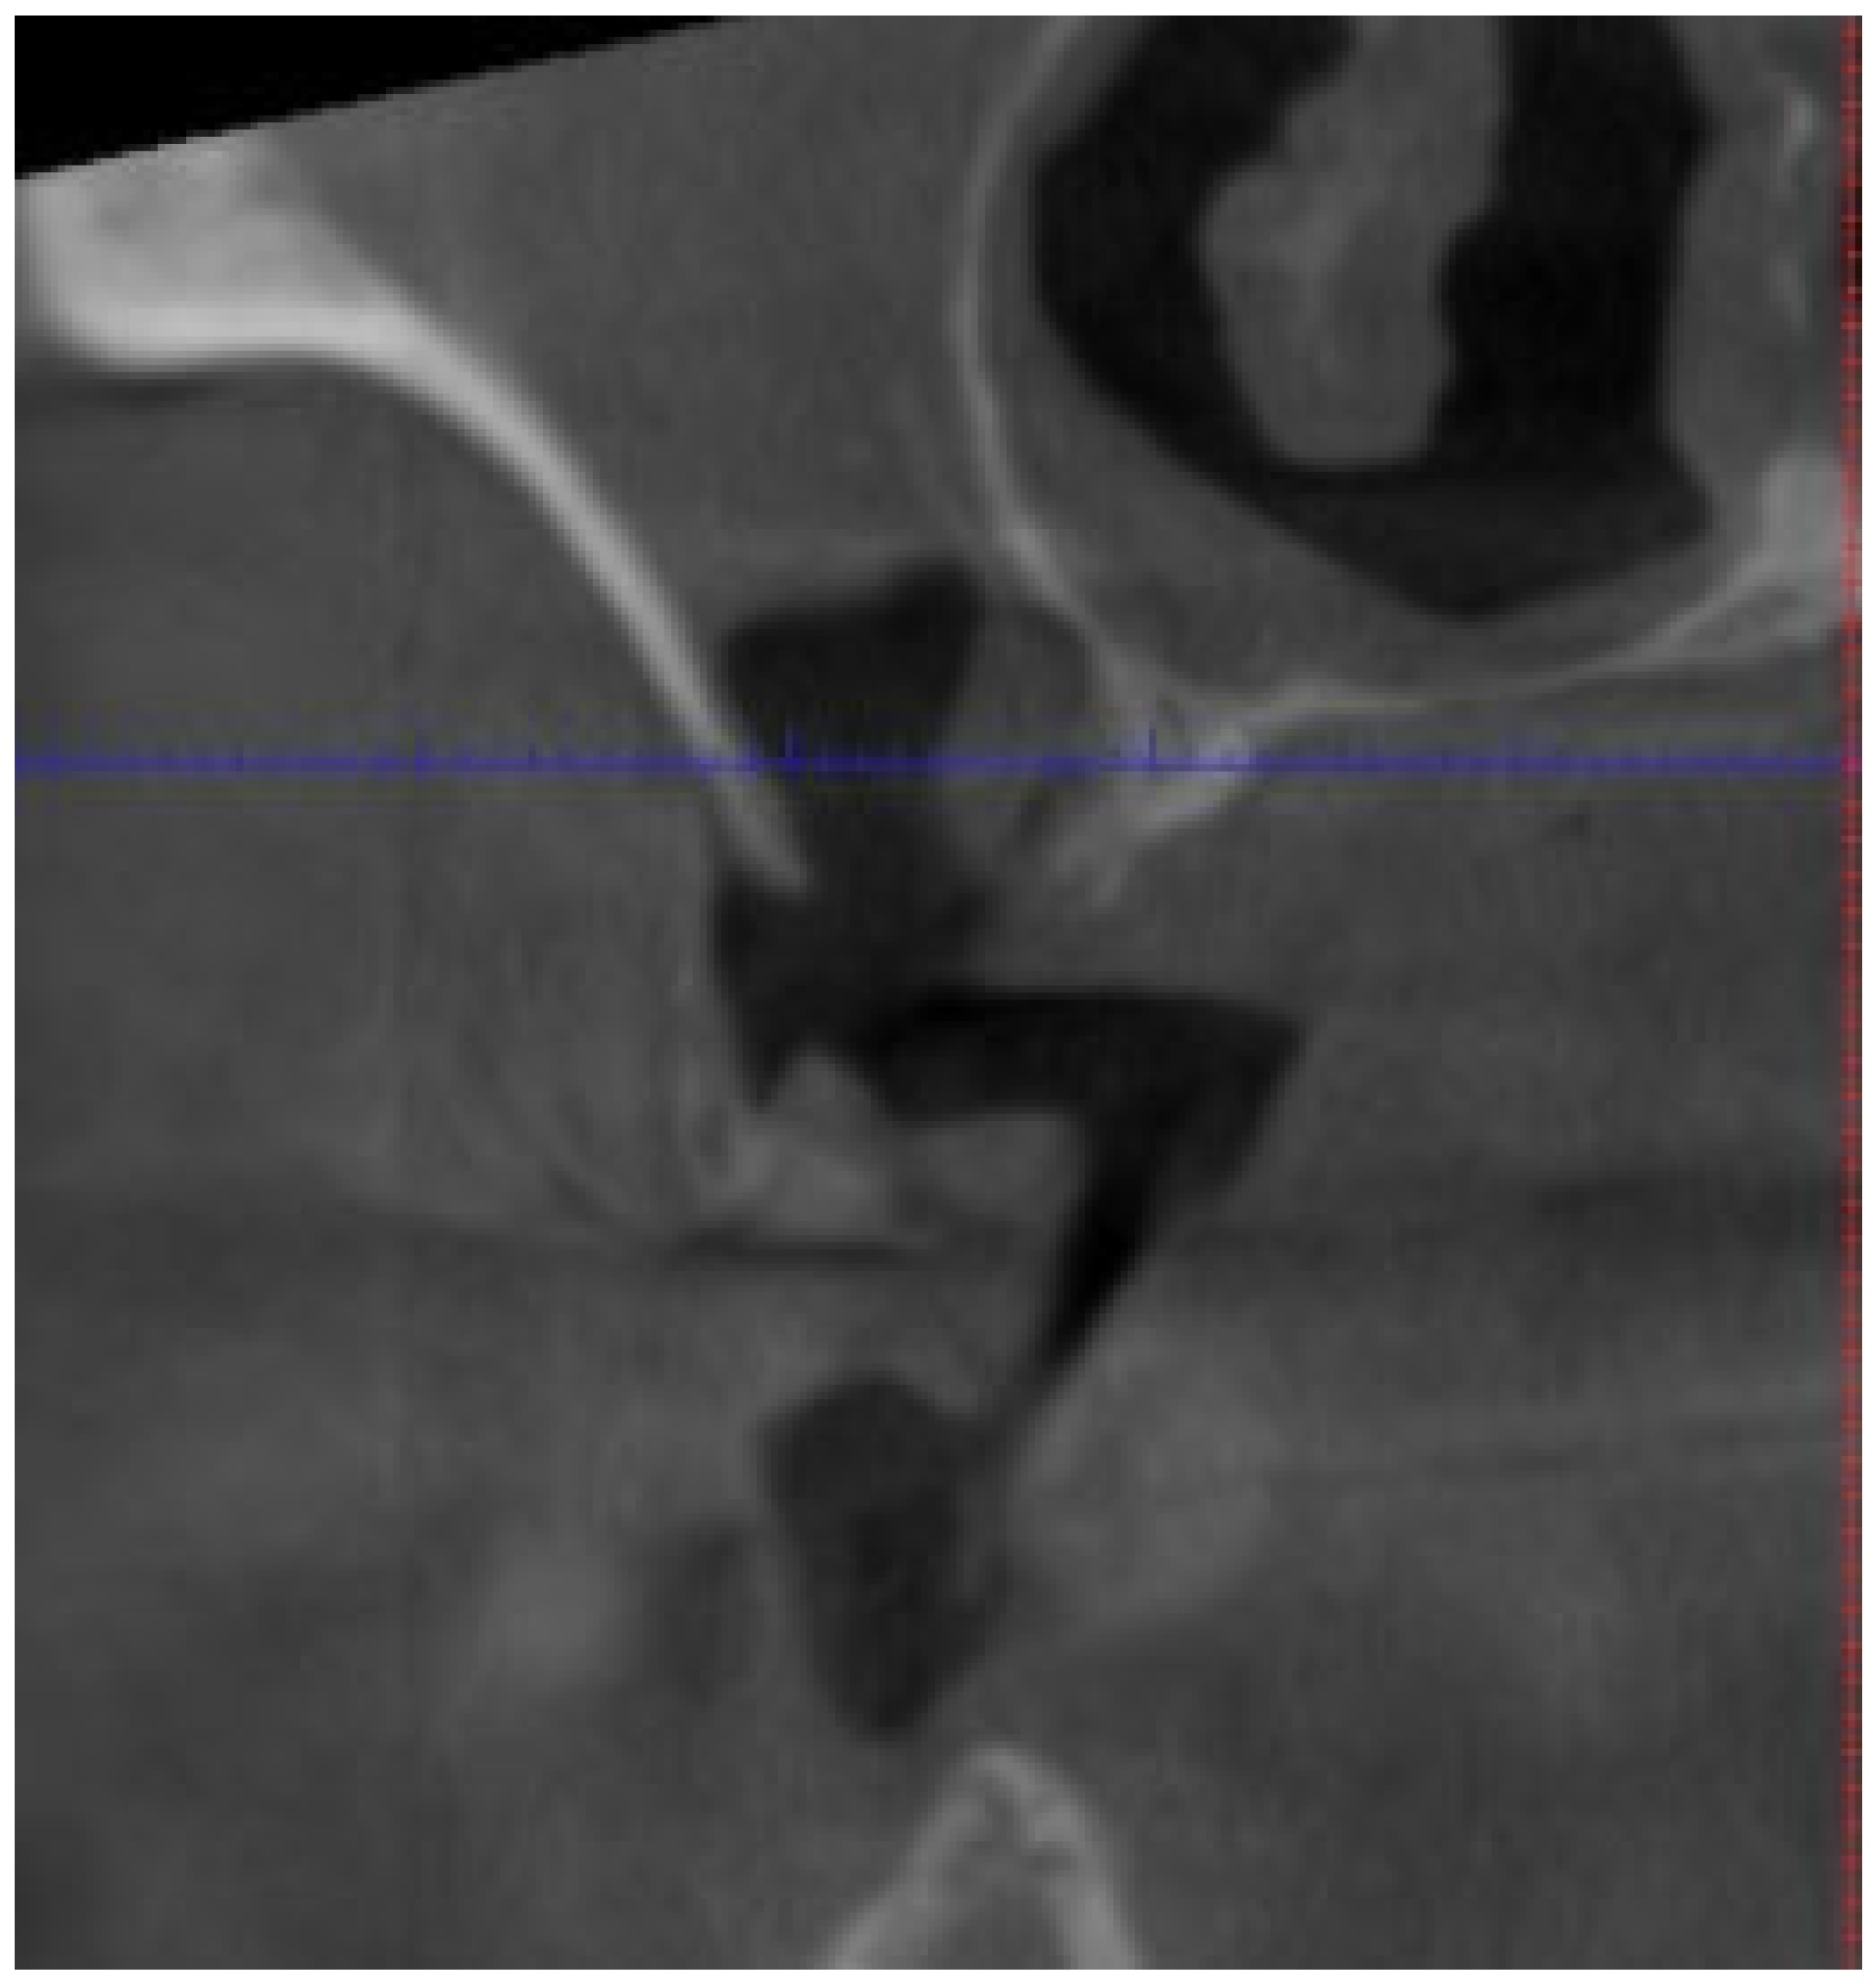

| Fistula (Intraoral/Extraoral) | An abnormal tract that connects the oral cavity (or skin) to necrotic bone, allowing probing of the underlying bone tissue (Figure 4). | Stage 1+ |

| Osteolysis Beyond Alveolar Bone | Bone resorption that extends beyond the alveolar process (e.g., affecting the inferior border, ramus, sinus floor, or zygoma), indicating severe bone involvement. | Stage 3 |